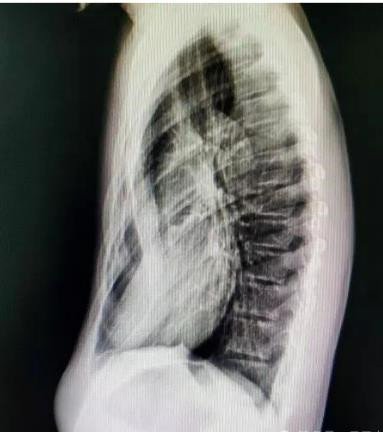

症状:胸骨及两侧肋骨向内凹陷,形成 “漏斗状” 畸形,幼儿期可能症状较轻,青春期随着身高快速增长,凹陷会逐渐加深,严重时胸骨可贴近脊柱。

若发现孩子胸口有凹陷,及时带娃到胸外科就诊,通过胸部 x 线、ct 扫描、肺功能测试、心脏超声等检查,明确凹陷程度和心肺受压情况,避免延误干预时机。